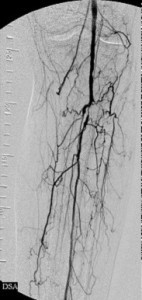

It was , therefore, helpful to the patient that I eliminate as much of the upstream disease as was feasible and dilate the critical stenosis of the left tibioperoneal trunk. Thus, balloon angioplasty was applied to the common femoral obstruction and the tibioperoneal trunk stenosis and a stent-graft was used to exclude from the circulation all the superficial femoral arterial disease. The bottom panel of images shows the immediate outcome of these interventions. The ulcer eventually healed.